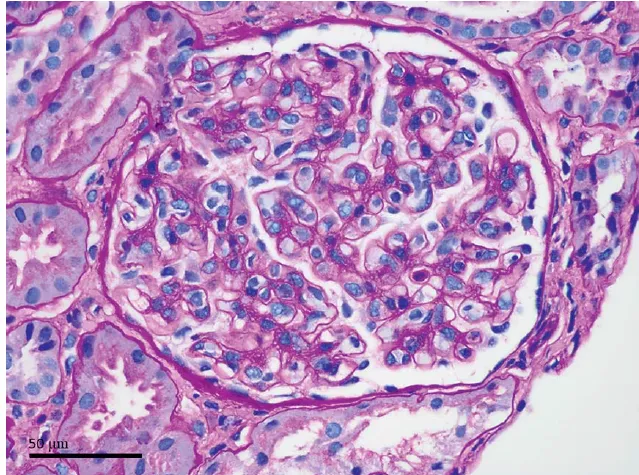

Foi realizado avaliação histopatológica do tecido urotelial, sendo identificou extensa metaplasia escamosa queratinizante (Figura 3). Diante do achado de alteração urotelial foi pensado que este seria o substrato anatômico para ITU recorrente.